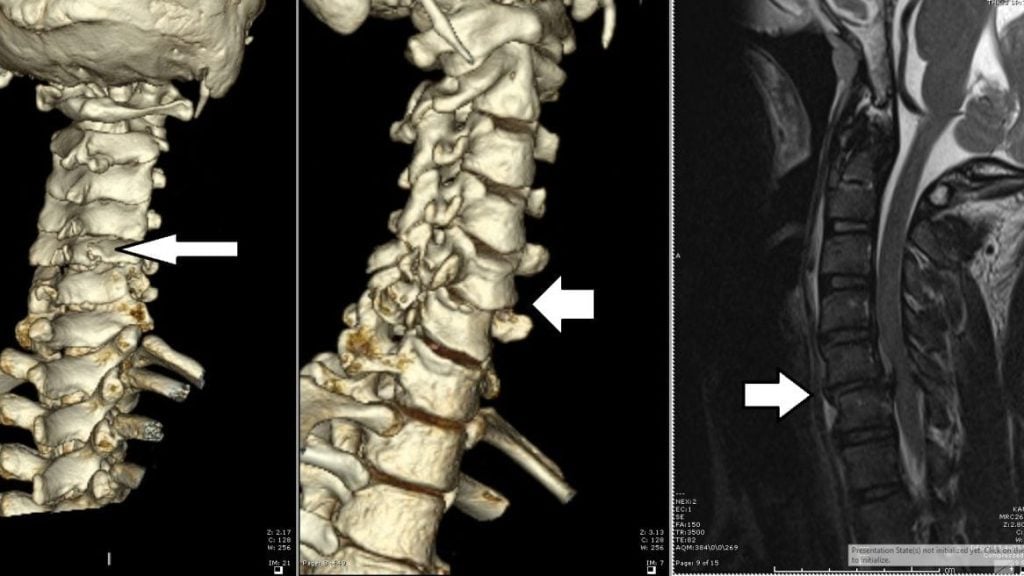

盛晓峰 / 脊椎伤者勿乱动 错误搬运恐瘫痪